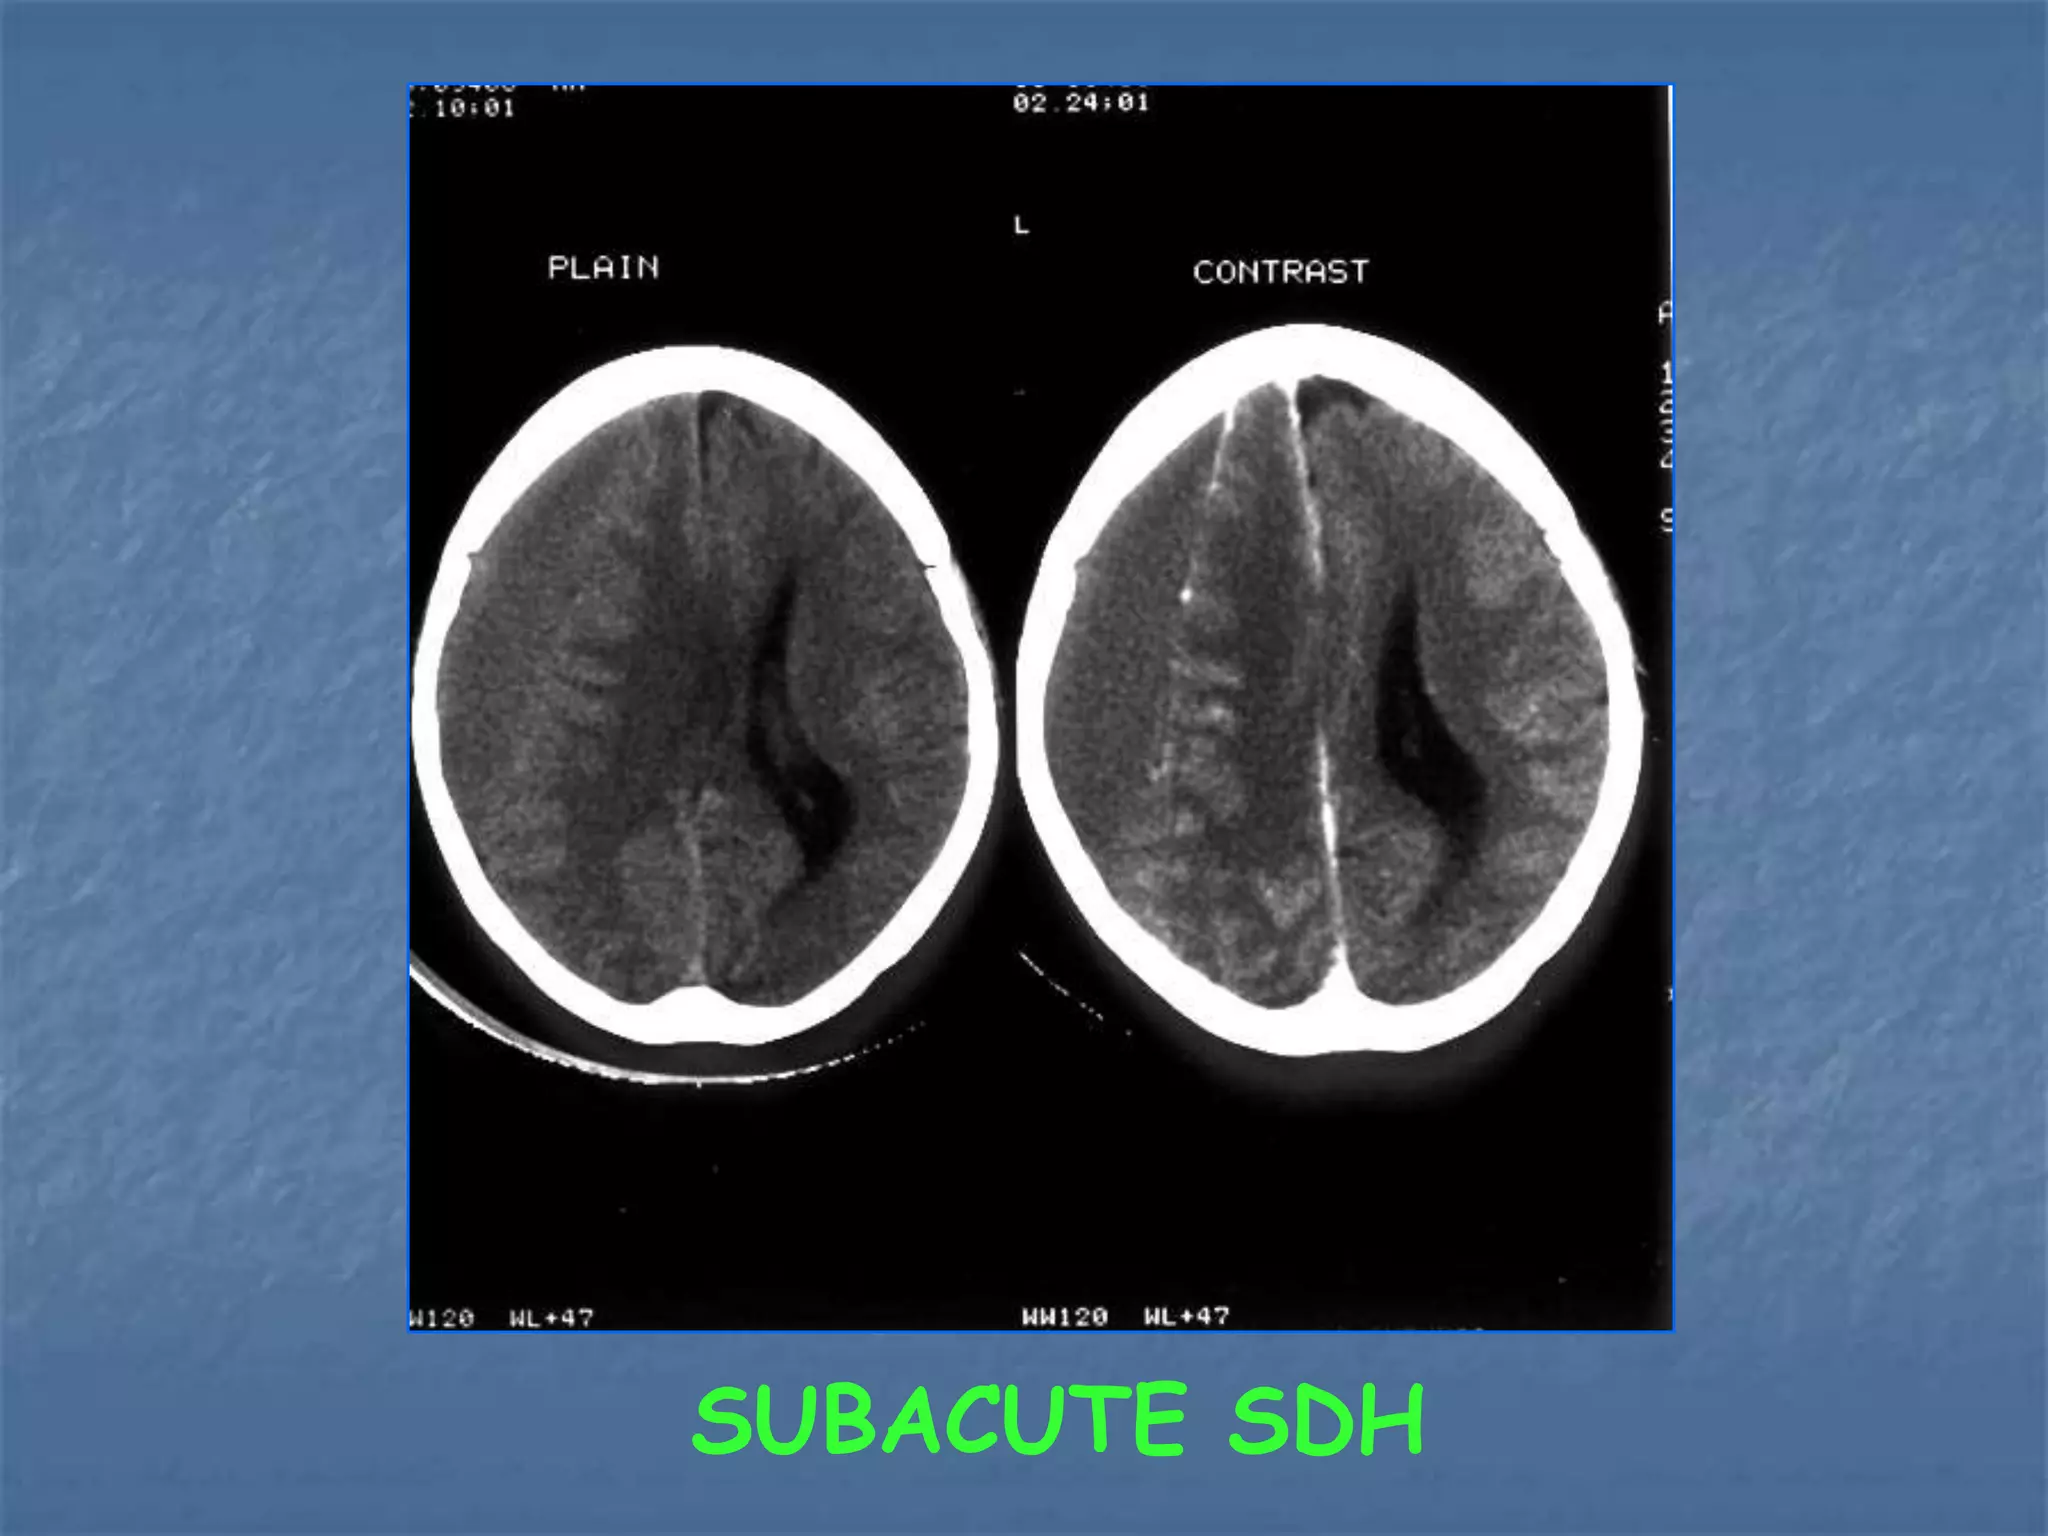

SUBACUTE SDH